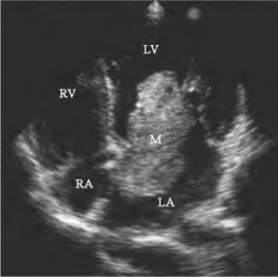

图15-1 左房黏液瘤二维超声图

心尖四腔见左房黏液瘤舒张期进入二尖瓣口,瘤体伸长呈长圆形或舌状(M)。LA左房